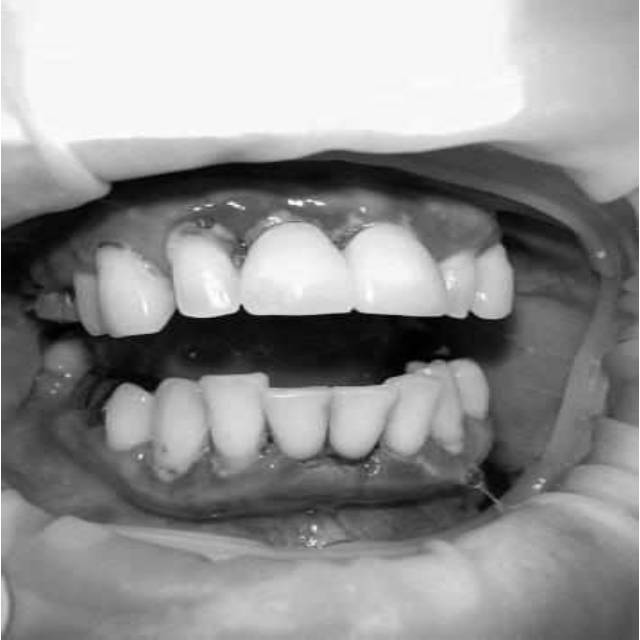

Ранее у пародонтолога не наблюдалась. При осмотре выявлены: неудовлетворительная индивидуальная гигиена полости рта, пародонтальные карманы до 7 мм, обильная кровоточивость и гноетечение из пародонтальных карманов, подвижность зубов 4.2, 4.1, 3.1, 3.2 II степени, обильные над- и поддесневые зубные отложения (рис. 1). На ортопантомограме отмечается резорбция костной ткани до ½ длины корня, очаги остеопороза (рис. 2). Пациенту был поставлен диагноз хронический генерализованный пародонтит тяжелой степени тяжести. При осмотре была составлена пародонтограмма с использованием компьютерного зондирования (рис. 3).

Рис. 1. Внешний вид

Через 6 месяцев при осмотре выявлен удовлетворительный уровень индивидуальной гигиены, отсутствие участков кровоточивости и гноетечения (рис. 4), пародонтальные карманы уменьшились в размерах (рис. 5). Пациент отмечает значительные улучшения. После стабилизации пародонтологического статуса пациент направлен для дальнейшего ортопедического лечения.

Рис. 4. Динамика результата через 6 месяцев